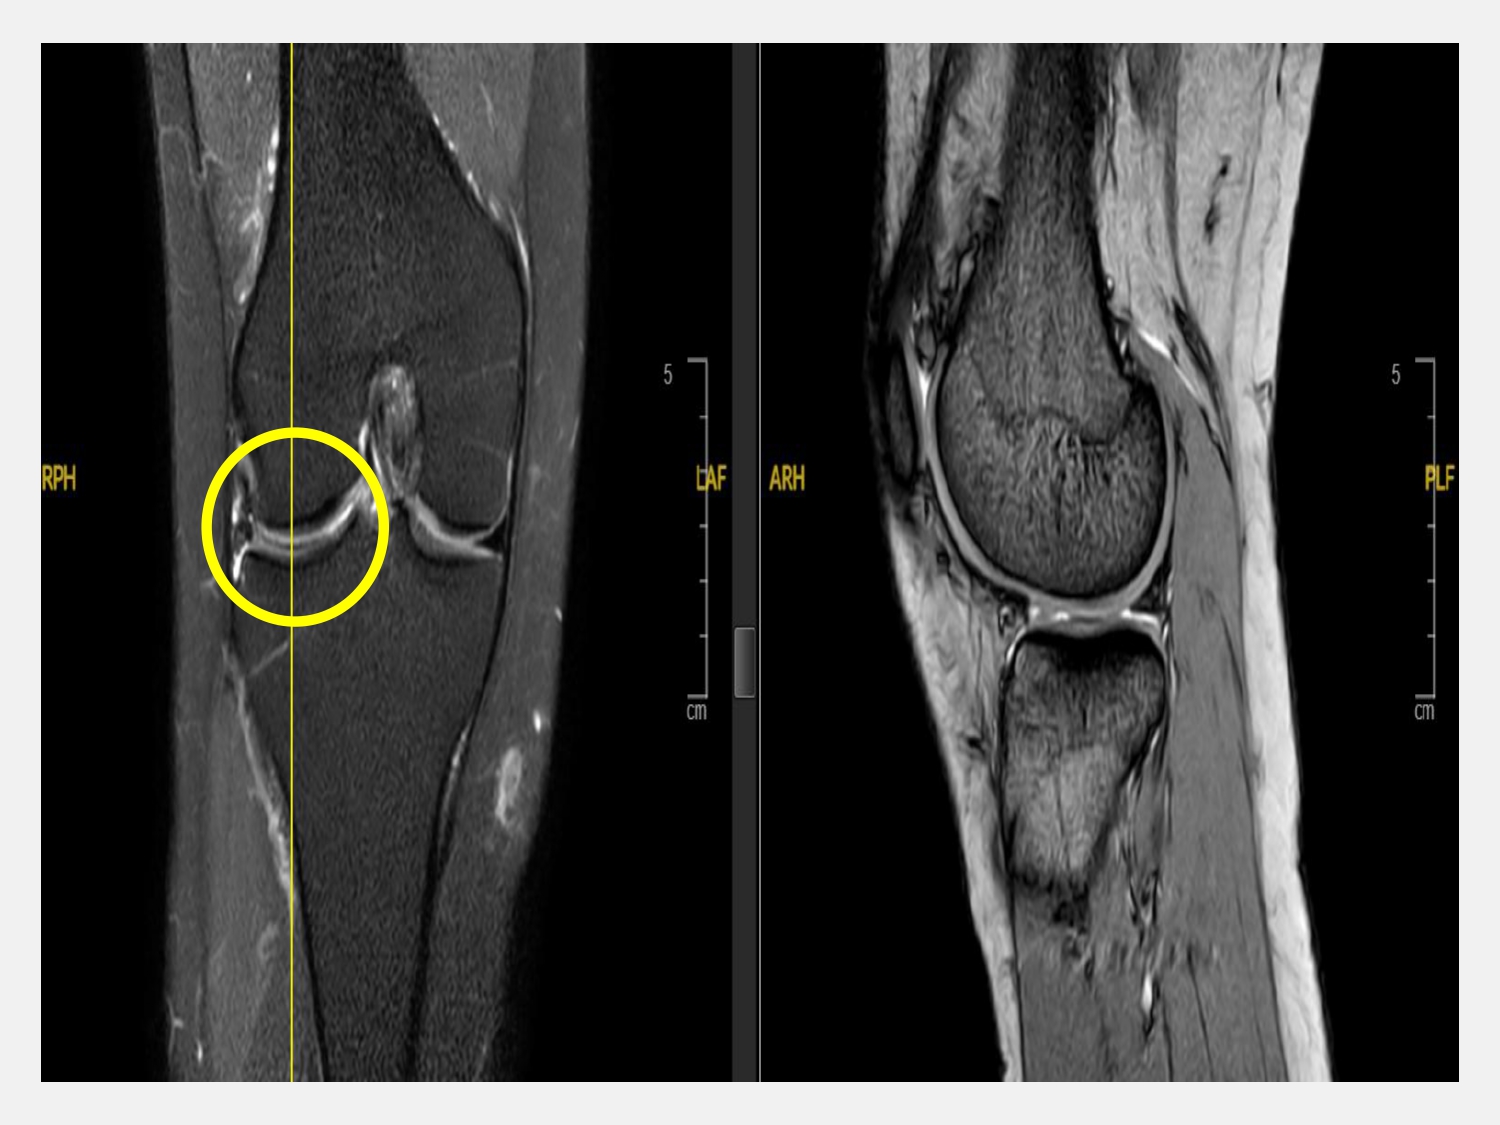

徐振恆進一步說明,如果半月板是相對簡單的破裂型態,目前已有良好的半月板修補工具可以處理,不管是影像或是關節鏡的追蹤都可以看到良好的癒合。但對於複雜型的半月板破裂或甚至是半月板都已經不見了,就需要比較困難的手術方法處理,包含半月軟骨的集中化處理、以自體肌腱移植來代替破裂的半月板或是商品化的半月板移植等。

徐振恆表示,劉先生這次接受的是「微創膝關節鏡輔助半月板修補手術」,在關節鏡的輔助下,以高強度的線材進行修補,將破裂的兩端進行縫合。手術的傷口只有2個1公分的小傷口,手術時間短幾乎沒有失血量。劉先生在手術後即可穿戴肢架護具保護下床活動,隔天就開始進行復健訓練。